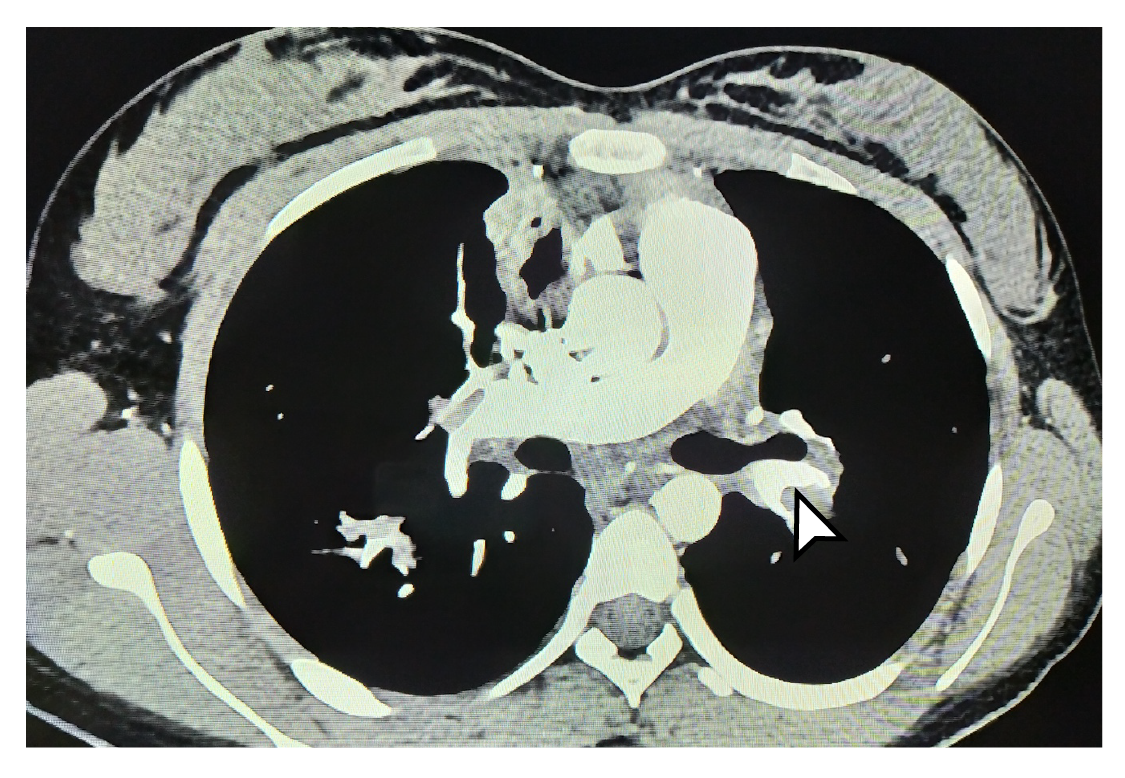

Los estudios se complementaron con tomografías de tórax y de abdomen con contraste, las cuales evidenciaron tromboembolia pulmonar grave (figuras 1 y 2) con múltiples trombos bilaterales, áreas pequeñas de infartos pulmonares, nódulos pulmonares múltiples, y embolia venosa renal bilateral con trombo que comprometía la vena cava superior. Se decidió reiniciar el tratamiento anticoagulante con heparina de bajo peso molecular, con lo cual los síntomas respiratorios mejoraron, lo que permitió dar de alta a la paciente y retomar el seguimiento por consulta externa.

Figura 2 Tomografía computarizada de tórax La flecha indica trombosis un gran trombo en la vena pulmonar izquierda. extensa de las venas pulmonares (derecha e izquierda).